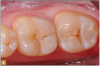

Giomer restoratives are bioactive regenerative materials that can be used where traditional direct composite materials are indicated. In the case presented in Figure 1, decay was noted on the occlusal surfaces of a first and second molar. What often looks like a very small amount of decay on the surface can lead to the discovery of significant dentin destruction. The quadrant was isolated and air abrasion was performed using 50 µm aluminum oxide (Figure 2). The occlusal groove enamel was abraded, revealing obvious decay to the dentin (Figure 3). Decay was identified with caries indicator and removed with a #2 round bur and slow-speed handpiece, with the goal of preserving as much healthy tooth structure as possible (Figure 4). Caries indicator stains denatured collagen and debris and helps to identify areas needing attention by the dentist, but equally importantly, it identifies areas without damage that can be preserved.

Fig 4. Caries indicator was used to ensure all decay was removed.

Figure 4